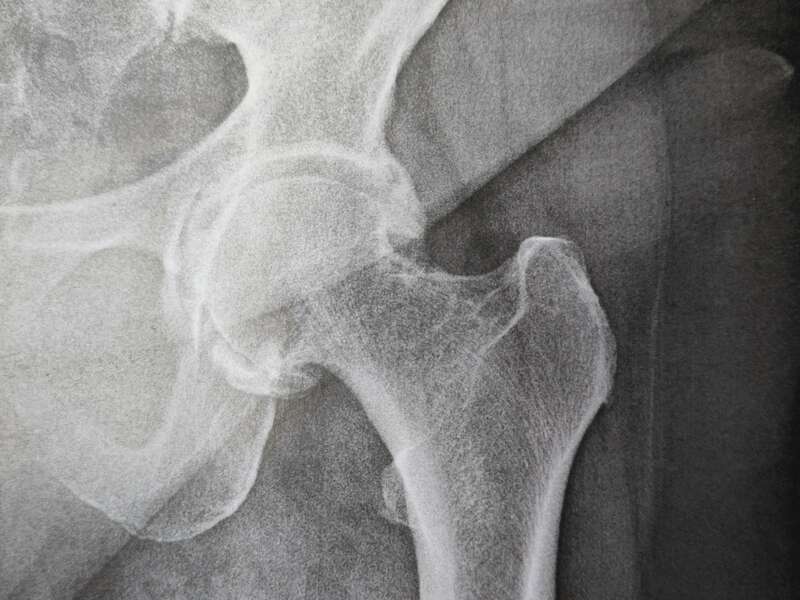

L’arthrose désigne un processus d’usure du cartilage liée au vieillissement. Ce n’est pas une fatalité liée à l’âge. Elle cause des dommages irréversible du cartilage qui perd au fur et à mesure son rôle de surface de glissement et d’amortisseur. La pression sur l’os s’accroît à mesure que l’épaisseur cartilagineuse diminue. Des excroissances osseuses, appelées ostéophytes, des kystes osseux et des ulcérations cartilagineuses se forment progressivement.

En réponse, la membrane synoviale devient inflammatoire et produit un liquide synovial. L’excès de pression articulaire et l’inflammation sont les causent des douleurs de hanche. La perte de congruence de l’articulation entraîne quant à elle, une diminution de la mobilité articulaire.

Elle sera confirmée par des examens radiologiques tels que des radiographies de hanche. En cas de doute diagnostic, afin d’éliminer un éventuel diagnostic différentiel, un scanner et/ou une IRM pourront être prescrits.